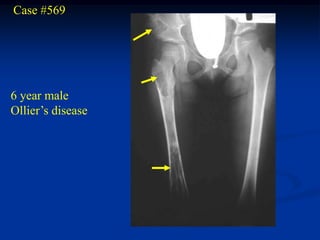

Case #569

6 year male

Ollier’s disease

Same patient